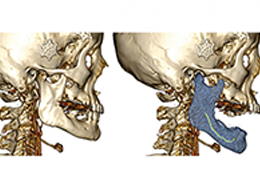

Everyone – including surgeons, patients and their loved ones – benefits from being better informed by the wealth of information buried within CT and MRI scans. Pro Surgical 3D gives surgeons more information to develop optimal treatment plans for patients. It also helps patients and their support group better understand their medical condition and proposed treatment options.

Better understanding of a condition, disease or diagnosis

Ability to clearly see the condition or disease

Better understanding of treatment options

High-quality and fast 3D reconstruction and 3D rendering

Instant and interactive surface extraction and export to STL and PLY formats.